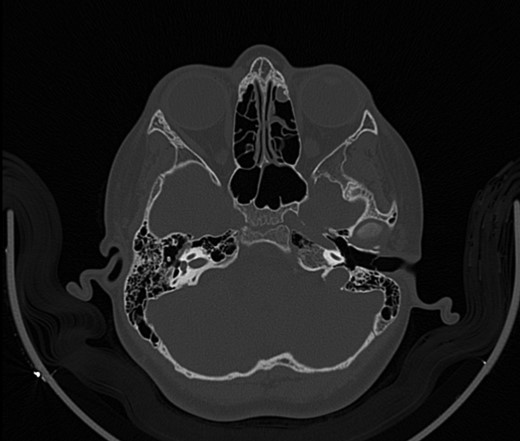

A 14-year-old male patient presented to the ENT clinic with bilateral hearing loss with no other otolaryngological symptoms. History from the patient stated a road traffic accident (RTA) 12 months ago. Meanwhile, the patient had no hearing problems prior to the RTA. Furthermore, detailed history of the accident revealed that the patient had no apparent skull injuries while pure tone audiometry (PTA) on presentation revealed bilateral conductive hearing loss and auditory brainstem response revealed right mild hearing loss and left moderate hearing loss. As a result, he was fitted with hearing aid for four months after presentation and was not compliant to it on the long-term. The patient is a non-smoker and is medically free with normal developmental milestones and negative family history of hearing complaints. Local examination of the ear revealed intact but minimally retracted tympanic membrane bilaterally. PTA was done in 2014 revealed right mild to moderate mixed hearing loss and conductive hearing loss at low frequency (Table 1). Meanwhile, the left ear had mild to moderate sensory hearing loss at high frequency (Table 2). The speech audiogram results show equal canal volume in both ears, less tympanometry pressure on the right ear and less compliance on the right ear (Table 3). The CT showed that both ossicular chains are deranged, and bilateral abnormal ossicles with no fracture or mass (Figures 1–3).

Figure 3:

CT mastoid, deranged left side ossicular disruption.